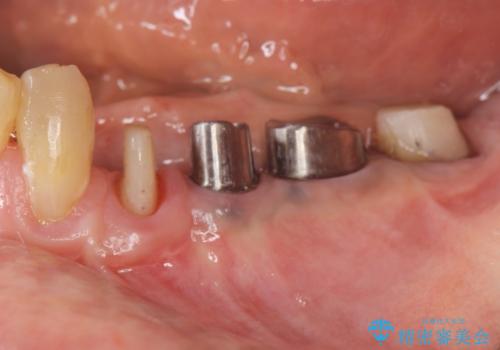

ブリッジ支台の歯の痛み インプラントによる咬合負担

- 以前治療したブリッジが噛むと痛く、食事ができないことの改善を希望され来院されました。

X線写真より、過度な咬合支持負担により支台となる歯の周囲の骨吸収が認められます。今後安定してしっかりとかめるような環境を整備するためにインプラント治療を選択しました。

ブリッジ治療は支台となる歯が弱いと、今回のように周囲の骨が吸収したり歯が割れてしまったりといったトラブルがおきます。咬合力に対抗するため、今回はインプラントを用いて機能回復を行いました。